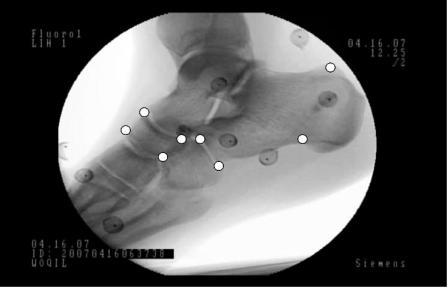

Funded by CFI ("Abnormal arthrokinematics and osteoarthritis"), the WOQIL was set up. This novel facility uses bi-planar fluoroscopic radiostereometric analysis (f-RSA) to resolve moving 3D bone position and orientation in-vivo to accuracies of +/-40 microns and 0.1 degrees. There is no error arising from skin motion, as is the case with optical motion analysis. Specifically I am using this system to study scapular-humeral kinematics in the shoulder, foot bone motion within footwear and joint kinematics in the osteoarthritic knee. This system can be used with or without implanted marker beads, allowing for healthy subjects to be studied.